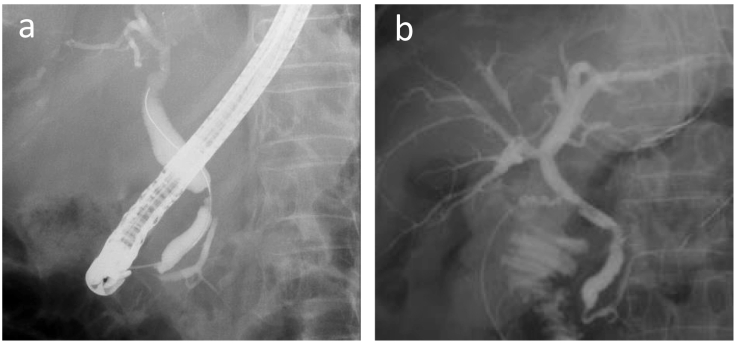

An abdominal computed tomography (CT) scan with dynamic enhancement revealed a 3-cm, ill-defined tumor in the pancreatic body circumferentially invading the CA and SMA (Fig. 1a,c,d,e). The portal vein (PV) was narrowed, and the splenic vein was obliterated by the invading tumor (Fig. 1b,d,e). Nine days after the initial check-up, the serum bilirubin level was 9.5 mg/dL, and endoscopic biliary decompression was done. The CBD was obstructed near the upper border of the pancreatic head (Fig. 2a). A 7 Fr-thick, 7 cm-long plastic internal stent tube was placed. A gadoxetic acid-enhanced magnetic resonance imaging did not reveal any liver metastases. The patient was diagnosed to have a T4N0M0 clinical stage III pancreatic tumor.

The expected effects of chemotherapy for LAPC prior to resection are (1) to provide a patient selection by testing the chemoresponsiveness of the tumor to identify aggressive diseases and to spare ineffective therapies and (2) to increase the complete resection rate by shrinking the tumor and treating micrometastases. As for surgical procedures after chemotherapy, almost all patients with LAPC with more than 180 degree of invasion to the CA and/or SMA spared combined resection of such major arteries ref. [13]. An accompanying merit of marked tumor contraction is to facilitate a limited resection, which can omit the combined resection of surrounding tissues and maintain the postoperative quality of life. In the present patient, among three important structures (CA, SMA, and CBD), only CA was resected with the tumor because such resection alleviates the complete removal of the tumor without reconstructive procedures, and CA was diagnosed as the most extensively involved by the tumor arising from the pancreatic body. The CBD obstruction was resolved prior to resection. The pancreatic head was preserved after confirming the absence of tumor cells at the pancreatic cut stump along the right border of the PV. An intraoperative fluorography via the cystic duct revealed a well-lumened CBD with slightly ragged margin, reflecting fibrotic tissue proliferation after the regression of the tumor by chemotherapy. It is well-documented that a neoadjuvant treatment causes extensive pathological changes in the pancreas, resulting in a higher extent of fibrosis and pancreatic atrophy ref. [16]. Pathology revealed the absence of invasion to the CA adventitia in the resected specimen. A collective study of 20 patients with DP-CAR reported such eliminating effect of chemotherapy ref. [17].